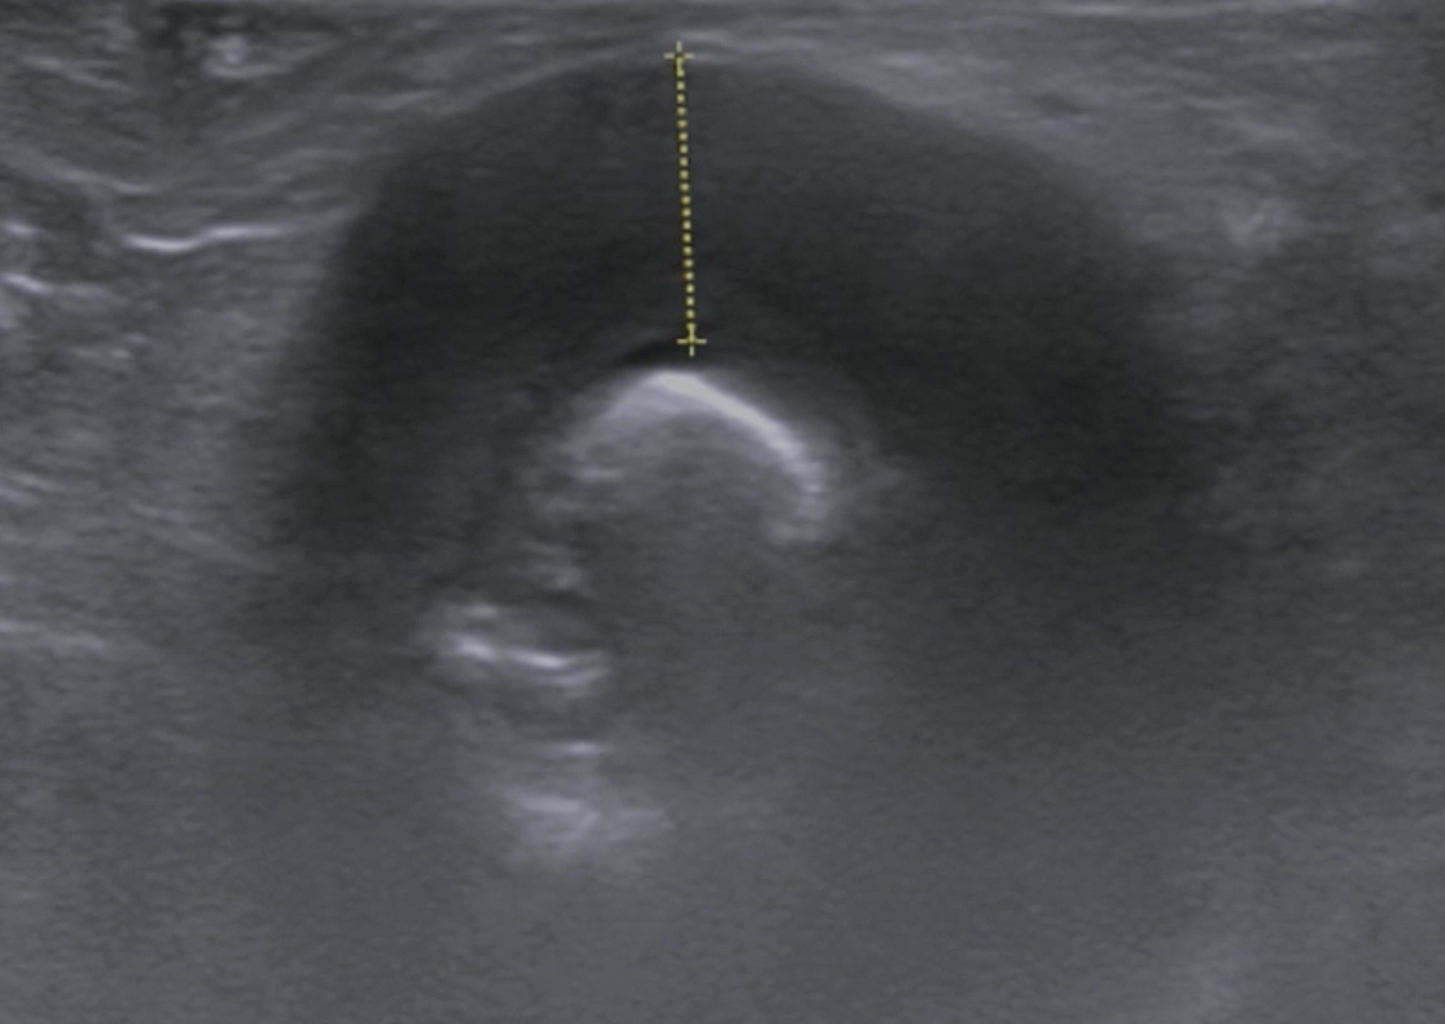

L'hématémèse et la méléna sont indicatives de saignements gastriques et / ou petits intestinaux, bien que les saignements occultes ne puissent être détectés que par des changements à l'examen hématologique suggérant une carence en fer. Les investigations incluent ensuite l'imagerie et l'endoscopie gastro-intestinale supérieure, mais les lésions au-delà de la portée de l'endoscope ne peuvent être identifiées que par endoscopie par vidéocapsule ou lors de la laparotomie. Du sang frais en présence d'une consistance normale des selles (hématochezia) indique un saignement colique focal. Souvent, une masse hémorragique est palpable à l'examen rectal numérique, mais une coloscopie peut être nécessaire.